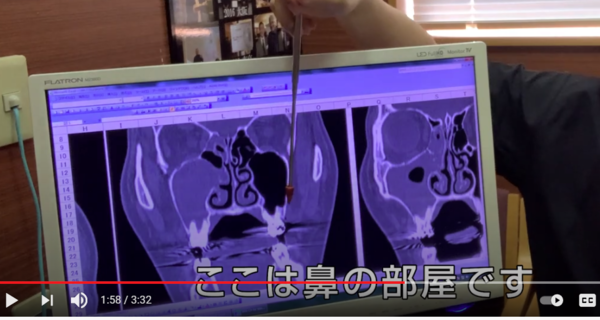

別の方のCT写真です。

歯の頭の位置で

輪切りではなく

縦に切って撮影した写真です。

ここに黒い部屋があります。

ここは鼻の部屋です。

つまり

硬いものが白くうつるわけですから

空気がある

鼻の部屋ですから

空気があるわけです。

指している

空気がないといけないところに

何かうつっていますね?